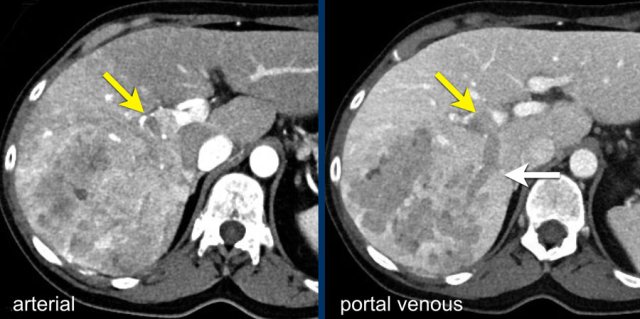

The images show an only mild rim-like arterially enhancing lesion in segment V with washout.

A linear area of hypoenhancement is seen extending from the mass which is suspicious of tumor in vein (yellow arrow).

Since we are not absolutely sure that it is a tumor thrombus, we cannot categorize this as LR-TIV.

A follow up CT was done, showing severe progression of the tumor as well as vascular involvement of the anterior right portal vein (white arrow).

Now we are sure of tumor invasion in the portal vein.